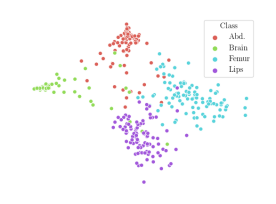

We compare the -distance of categorical features and domain features. Fig. 5 (a) shows that domain difference is higher in domain features than in categorical features. This indicates that domain features contain more domain information whereas categorical features are more domain-invariant. Fig. 6 shows the t-SNE plot of categorical features in both domains for MIDNet. From Fig. 6 (a), we observe that the categorical features learned by MIDNet enable the anatomical classification. Fig. 6 (b) shows that the learned categorical features are domain-invariant.

In addition, we utilize t-SNE plots for feature visualization in Fig. 10. Comparing Fig. 10 (a) and Fig. 10 (b), we observe that with mutual information disentanglement, (1) samples from the same category are more tightly clustered (see the top row) and (2) the source domain and the target domain are overlap more (see the bottom row). This indicates that mutual information disentanglement is important for learning categorical-focused and domain-invariant features. Fig. 10 (a), (c)-(d) show that the proposed method outperforms other state-of-the-art methods for learning category-discriminative and domain-invariant features, especially for unseen categories in the target domain (e.g., (a) vs. (d)).